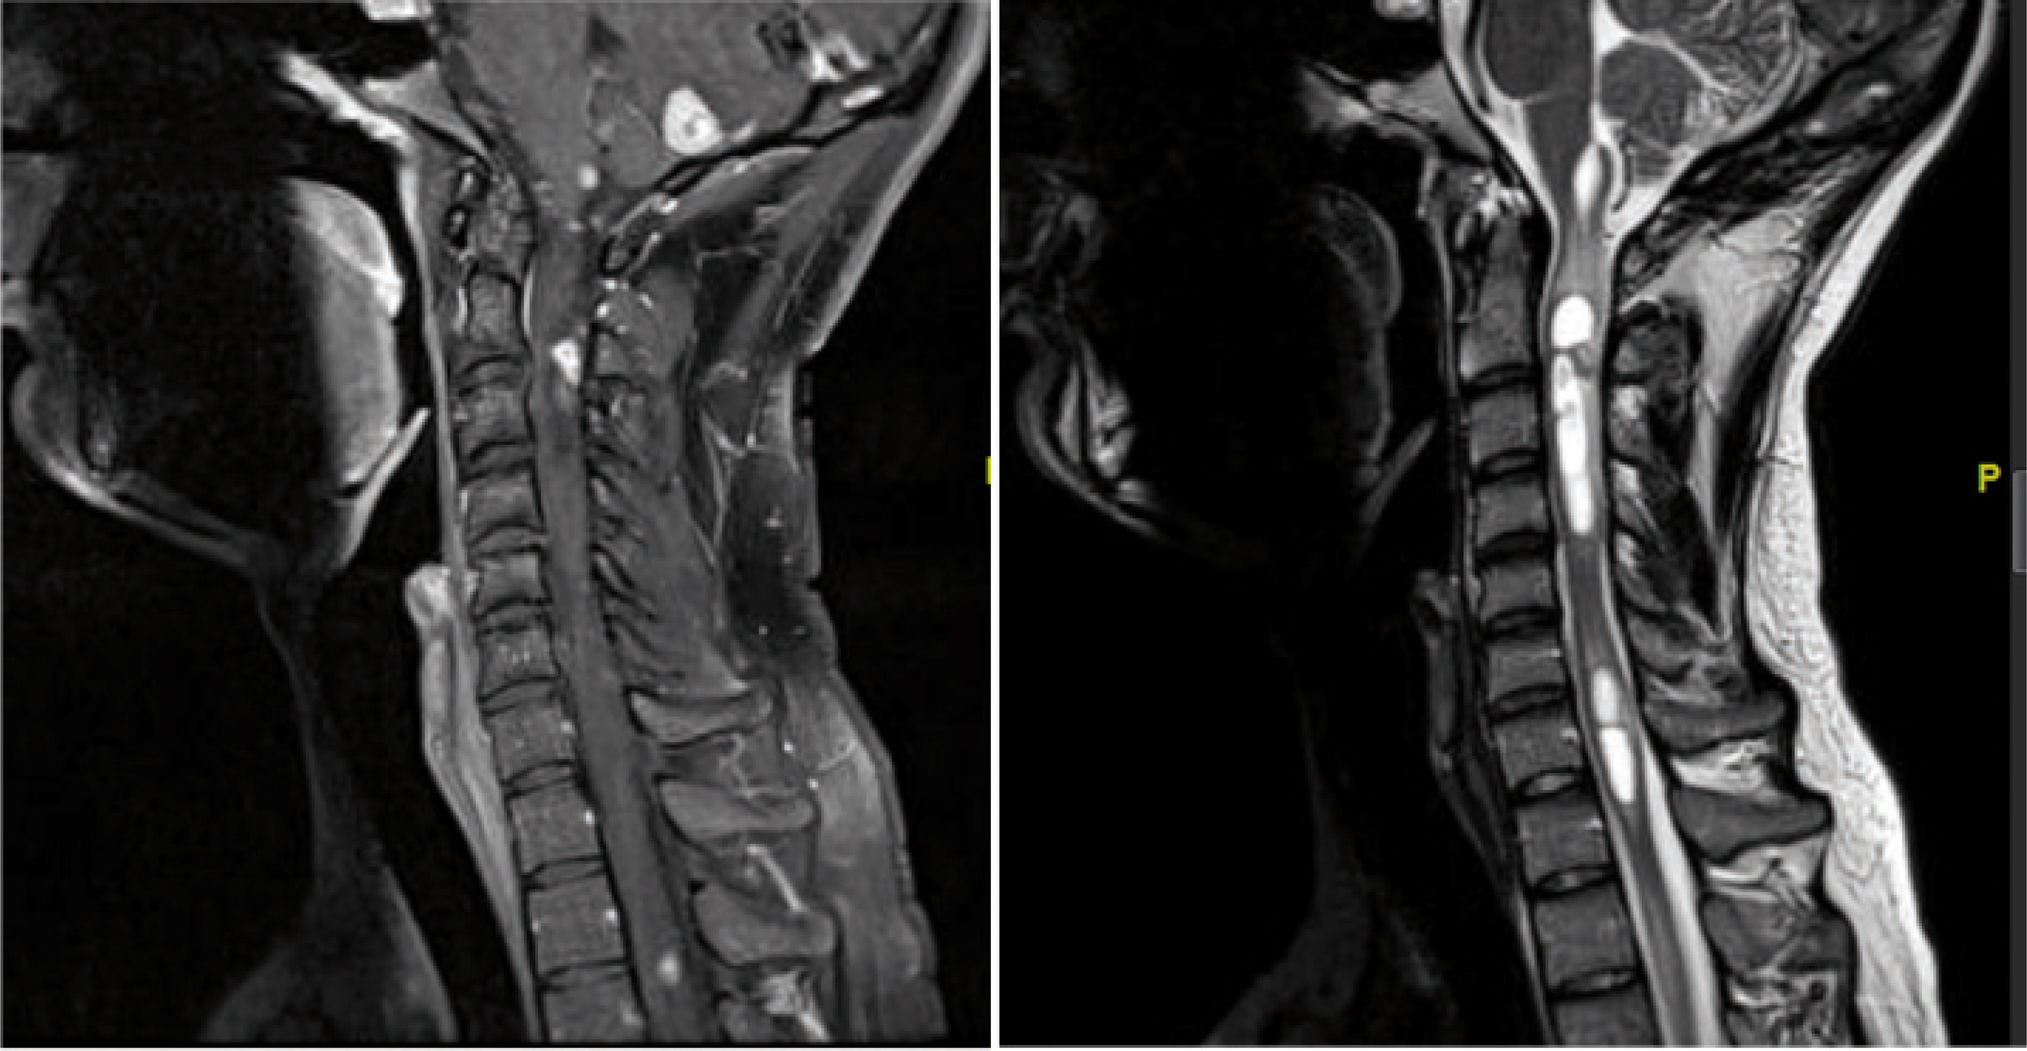

HB represents one of the earliest manifestations of VHL syndrome (11). Gadolinium-enhanced magnetic resonance imaging (MRI) is the best diagnostic modality for HB because its resolution is markedly superior to CT (46, 47). They appear as homogenously enhancing lesions and are sometimes associated with a cystic component. Hemorrhage might be present. Tumors can be seen in the brainstem, cerebellum, or spinal cord (Figure 1). Spinal cord lesions can exist on the pial surface as small enhancing nodules or intramedullary with associated syrinx. Symptomatic spinal HB are often associated with syrinx and edema (48). Larger spinal HB are more likely associated with flow voids compared to smaller HB (48). Patients who are known to be at risk for VHL can be screened with MRI of the neural axis. Similarly, if a lesion is noted on brain MRI, then an MRI of the spine is recommended.

Fig 1

Figure 1. Sagittal MRI of posterior fossa and cervical spine. Left: T1 with gadolinium shows multiple enhancing HB tumors involving cerebellum, brainstem, and spinal cord. Right: T2 MRI shows multiple intramedullary cystic lesions consistent with VHL hemangioblastoma.